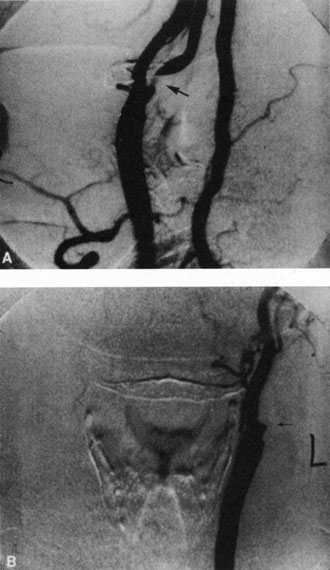

Two types of microemboli are associated with carotid artery disease. The first is cholesterol emboli, which are a bright yellow or orange color, often irregular in shape, and appear slightly larger than the blood column; these are called Hollenhorst or bright plaques (Fig. 10). They tend to lodge at the bifurcation of medium and small vessels but can also change position, moving downstream from one bifurcation to another. They generally do not produce complete retinal artery obstruction but can produce localized partial obstruction of the arteriole, which is sometimes accompanied by dilation of the adjacent vein.188 Transient obstructions producing amaurosis fugax are common.189 Some of these emboli remain unchanged for long periods, whereas others disappear. In some patients, an inflammatory segmental perivascular cuff gradually appears at the site of cholesterol lipid embolus, sometimes obscuring the embolus (Fig. 11).188,190 This periarteriolar sheathing is probably due to endothelial cell damage and sometimes disappears with time, leaving a narrowed blood column.189 Digital pressure on the eye occasionally causes the embolus to “flash” and become more apparent191; further pressure sometimes causes the embolus to move toward the optic disc as the central retinal artery partially collapses. At times, after the embolus has ophthalmoscopically disappeared, fluorescein angiography provides evidence of microembolization in the form of a focal area of arteriolar leakage (Fig. 12).192

Fig. 12. A: Ophthalmoscopy shows no emboli in the left eye of a patient who had experienced an episode of amaurosis fugax. B: No abnormality is seen during the arteriolar phase of the angiogram. C and D: In the venous and recirculation plates, fluorescein leakage is seen at arteriolar bifurcation, indicating endothelial damage caused by microemboli (arrows). (Courtesy of William F. Hoyt, M.D.)